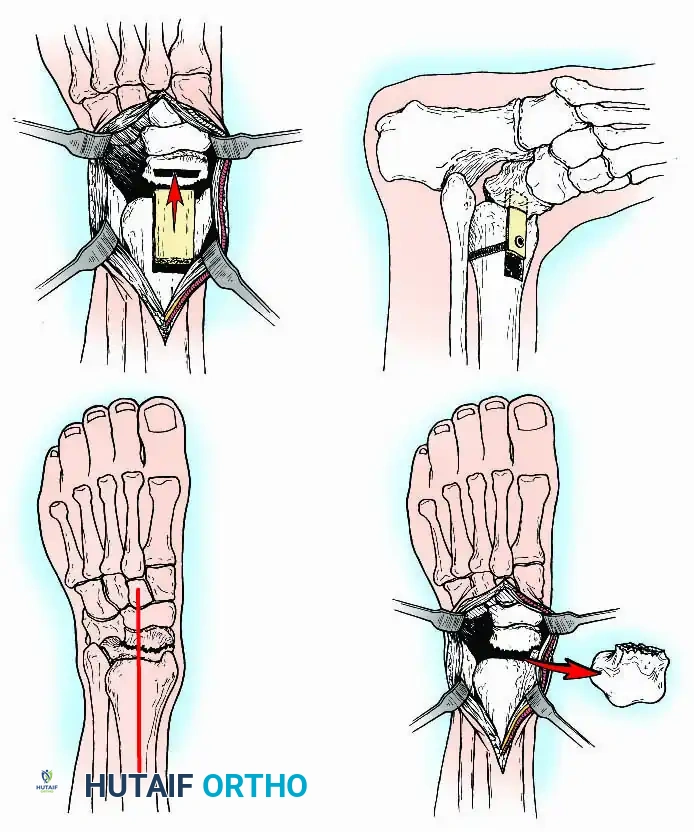

Preparation of Joint Surfaces

Two primary philosophies exist for joint preparation:

- Contour Preservation (Fishscaling): The remaining articular cartilage is meticulously denuded using curettes, and the subchondral bone is "fishscaled" or aggressively petalled with a sharp osteotome. This preserves the native ball-and-socket contour of the ankle, maximizing inherent bony stability and minimizing limb shortening.

- Planar Resection (Parallel Cuts): Two parallel cuts are made—one through the distal tibial plafond and one through the talar dome—using an oscillating saw. This technique resects a minimal amount of bone but creates perfectly flat, highly vascular cancellous surfaces that allow for excellent apposition and easy posterior translation of the talus. Extramedullary alignment guides (often repurposed from total knee arthroplasty systems) can be utilized to ensure precise, parallel resections.

Internal fixation is currently the preferred method for uncomplicated ankle arthrodesis due to higher union rates, superior patient comfort, and the elimination of pin-tract infections. Biomechanical studies demonstrate that crossed, large-diameter (6.5 mm or 7.3 mm) cannulated cancellous screws provide exceptional resistance to shear and torsional forces.

A standard construct involves two or three screws:

1. A "home run" screw directed from the posterior malleolus into the anterior neck of the talus.

2. A screw from the medial malleolus into the lateral body of the talus.

3. A screw from the anterolateral tibia into the medial talar body.